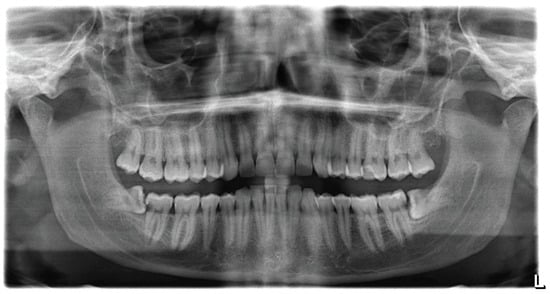

2.4. Radiographic Documentation